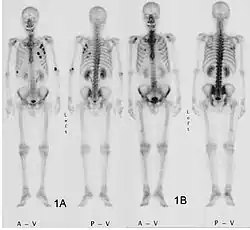

Метастазы при колоректальном раке на сцинтиграммах до (1A) и после (1B) химиотерапии